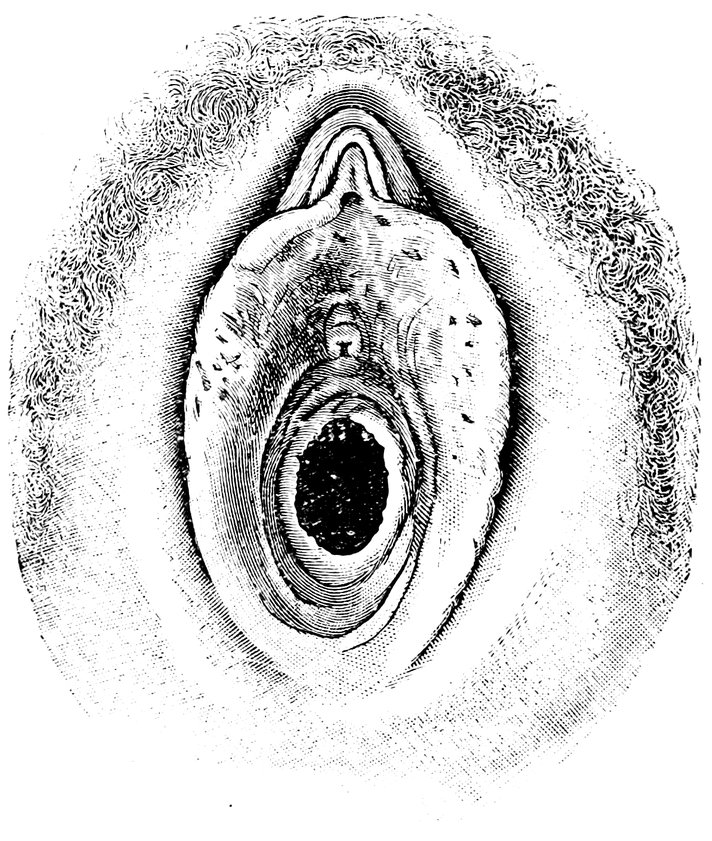

| 18. | Annular Hymen | 64 |

| 19. | Annular Hymen | 64 |

| 20. | Semilunar Hymen | 65 |

| 21. | Annular Hymen with Congenital Symmetrical Indentations | 65 |

| 22. | Fimbriate Hymen | 65 |

| 23. | Deflorated Fimbriate Hymen | 65 |

| 24. | Septate Annular Hymen | 67 |

| 25. | Septate Semilunar Hymen | 67 |

| 26. | Extremely tough Annular Hymen with an obliquely disposed Septum | 67 |

| 27. | Septate Hymen with Apertures of unequal Size | 67 |

| 28. | Septate Hymen with Apertures of unequal Size | 68 |

| 29. | Hymen with rudimentary Septum | 68 |

| 30. | Hymen with posterior rudimentary Septum | 68 |

| 31. | Labiate Hymen with posterior rudimentary Septum | 68 |

| 32. | Hymen with anterior rudimentary Septum | 69 |

| 33. | Hymen with anterior rudimentary Septum projecting in a opiniform Manner | 69 |

| 34. | Hymen with anterior and posterior rudimentary Septa | 69 |

| 35. | Hymen with filiform Process projecting from the anterior Margin | 69 |

| 36. | Hymen in which there are two symmetrically disposed thinned Areas. The left of these is perforated | 69 |

| 37. | Very unusual form of Hymen | 70 |

| 38. | Semilunar Hymen with cicatrized Lacerations in its Border | 70 |

| 39. | Deflorated Semilunar Hymen with laterally disposed symmetrical Lacerations | 70 |

| 40. | Deflorated Annular Hymen with several cicatrized Lacerations | 70 |

| 41. | A. Septate Hymen in which defloration has been effected through one of the Apertures. U. Urethra. Cl. Clitoris. H. Cicatrized Margin. C. Septum. B. Lateral view of Septum | 70 |

| 42. | Deflorated Septate Hymen | 71 |

| x43. | Hymen with larger anterior and smaller posterior Apertures | 71 |

| 44. | Carunculæ Myrtiformes in a Primipara | 71 |

| 45. | Vaginal Inlet of a Multipara, without Carunculæ Myrtiformes. Slight Prolapse of Anterior and Posterior Vaginal Walls | 71 |